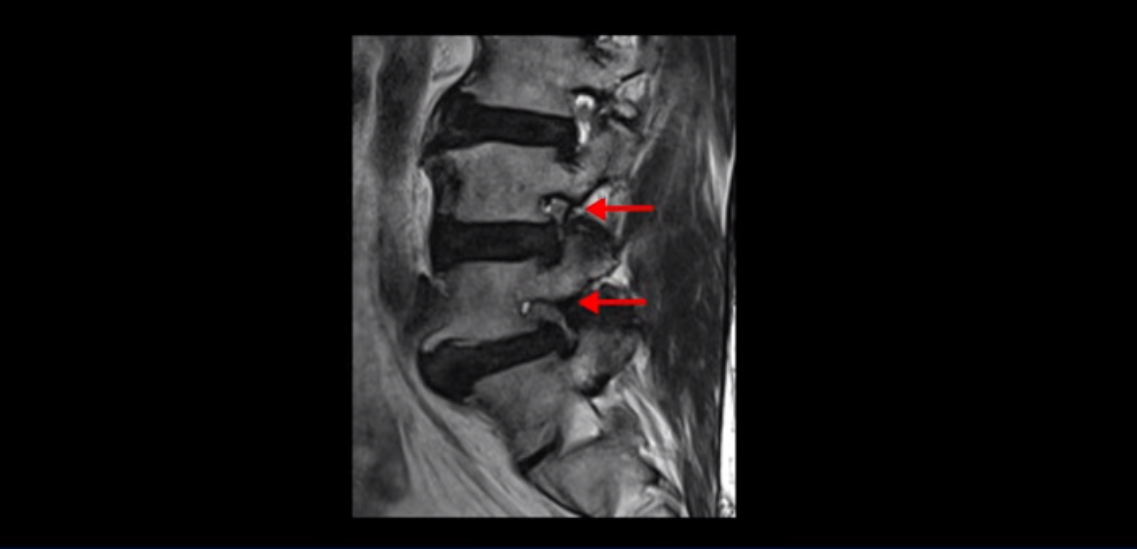

이 환자분은 협착증 수술을 두 번 받은 뒤에 또 다시 다리 방사통이 심해지고 발목 마비 증상(풋드랍)이 생겨서 이번에는 유합술을 권유받은 환자분입니다. 먼저 MRI를 보고 설명해 드린 후 이런 환자분의 방사통과 발목의 마비와 힘 빠짐이 어떻게 수술 없이도 좋아질 수 있는지 그리고 치료는 어떻게 하는지 자세히 설명드리겠습니다.

이분은 허리 다섯 마디 중 4번 5번, 5번 1번에 감압술로 눌린 신경을 풀어주는 수술을 받았습니다.

5번 1번도 왼쪽 후궁을 열고 수술 받았습니다.

하지만 중심성 협착은 여전히 심한 상태입니다.

이분은 오른쪽, 왼쪽 다리에 모두 방사통이 심하고 왼쪽 다리에 마비 증상, 즉 풋드랍(족하수) 증상이 있습니다. 왼쪽 신경 가지가 빠져나가는 추간공을 보면 두 마디가 좁아져 있습니다.

이런 신경 구멍이 좁아져 있는 걸 협착이라고 합니다.

이미 앞선 두 번의 수술로 뼈와 인대 등을 일부 제거해서 안정성이 떨어진 상태에서 추가로 수술하려니까 척추가 너무 불안정해져 무너질 게 걱정되니까 이번에는 나사 박는 유합술을 권유 받은 겁니다. 이런 환자분들의 방사통과 마비 증상이 어떻게 수술 없이 좋아질 수 있을까요? 치료는 어떻게 하는 걸까요?